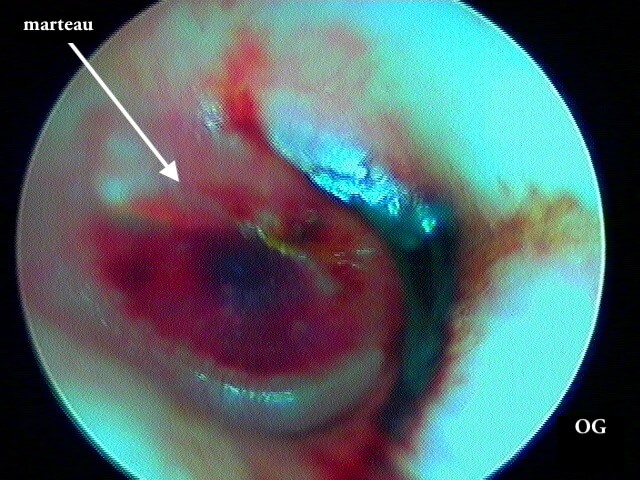

3/4 post otitique récente

Ici une otite séromuqueuse gauche perforée cicatrisée à 1 mois (cicatrice inférieure)

Une otite séromuqueuse droite perforée (et non otite moyenne aiguë)